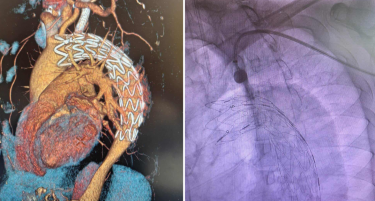

ПРВПАТ ВО МАКЕДОНИЈА ВО „АЏИБАДЕМ СИСТИНА“ ИЗВЕДЕНА КОМПЛЕКСНА ЕНДОВАСКУЛАРНА ПРОЦЕДУРА НА ТОРАКАЛНАТА АОРТА – ТЕВАР СО Т.Н. IN SITU ФЕНЕСТРАЦИЈА

29 Октомври, 2025 16:58